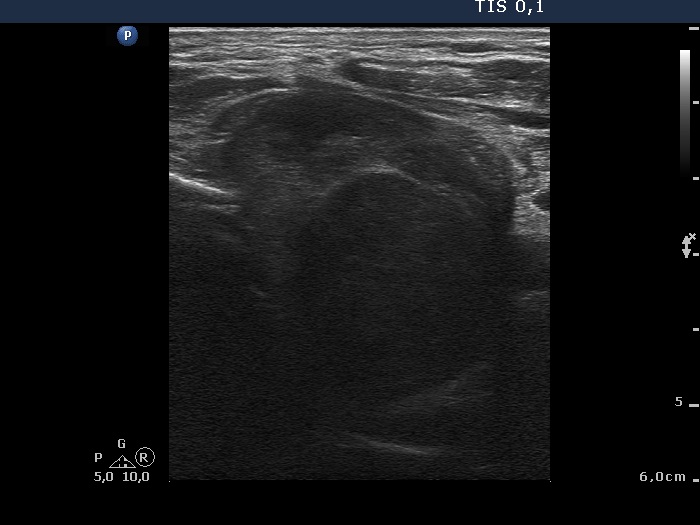

Anaplastic carcinoma - Case 12. (ultrasonographic picture 3)

Left lobe, horizontal scan. A large hypoechogenic nodule occupies almost the entire left lobe. The dorsal and lower part of the tumor cannot be judged.